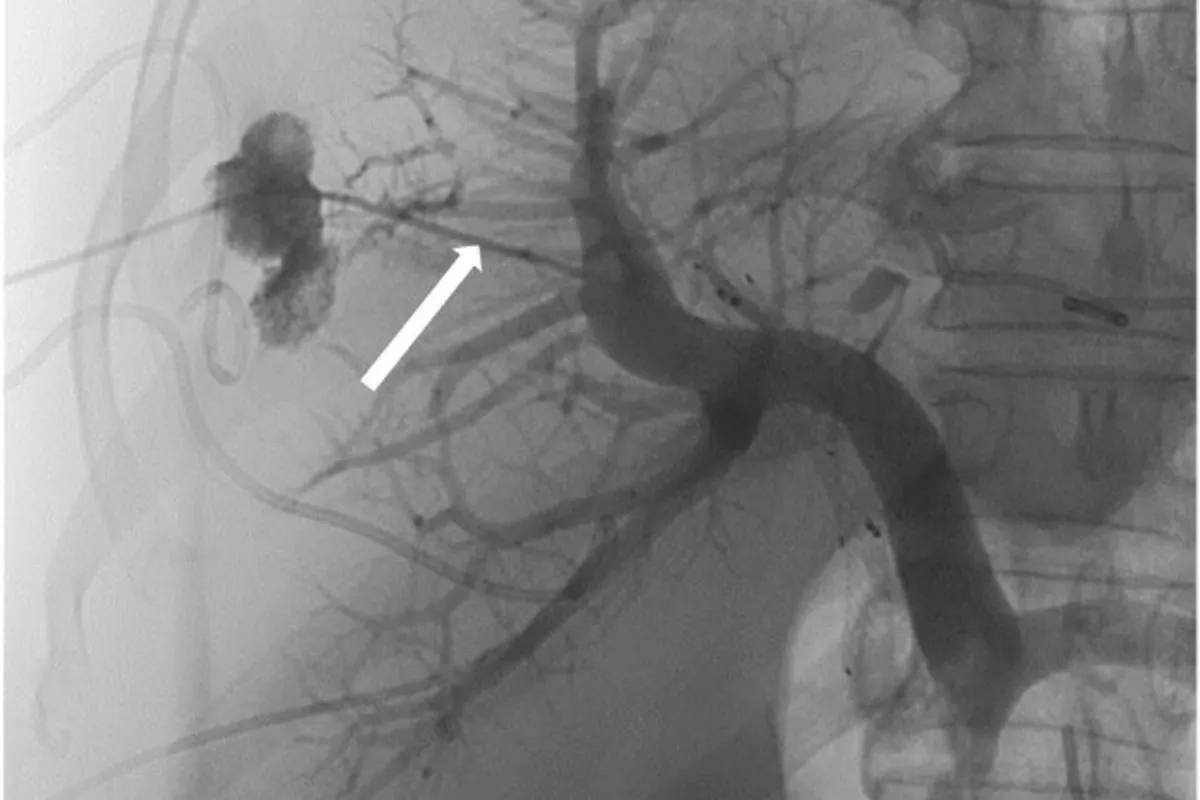

Interventional Radiology (IR) uses real-time imaging such as X-ray, ultrasound, CT, or MRI to guide tiny instruments through the body for treatment — without large surgical incisions.

Common Interventional Radiology Procedures